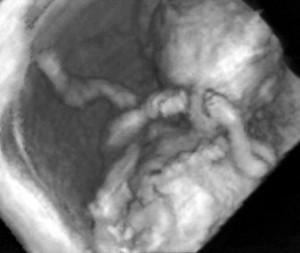

Второй триместр: быстрый рост и развитие движений

К 14-й неделе плод достигает примерно 14 сантиметров. Укрепляются костные структуры, пальцы рук и ног полностью разделены, формируется мимика и движение глаз. Мозг координирует всё больше процессов, и плод начинает активно исследовать пространство — движениями, реакцией на свет и звуки.

Слух, вкус и ощущения

В 18 недель начинает функционировать пищеварительная система: плод начинает заглатывать амниотическую жидкость. Уже в этот период женщина может почувствовать первые толчки. На более поздних сроках плод способен различать вкусовые оттенки жидкости, что помогает ему адаптироваться после рождения.